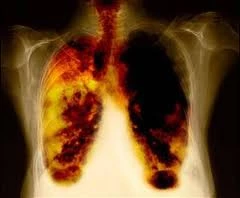

Kanserde tedaviden daha önemli olan husus kanserin önlenmesidir. Önlemede karsinojenik (kanser yapıcı) maddelerden uzak durmak, temiz ve sağlıklı yasamak, spor ve egzersiz yapmak ve uygun bir diyet uygulamak gibi hususlara uyulması kanser sıklığını rahatça yarıya indirebilir. Kanserin en önemli nedenlerinden biri olan sigaraya ayrı bir paragraf açmak gerekir. Tüm dünyada her yıl yaklaşık dört milyon ölüm sigaraya bağlı nedenlerle meydana gelmektedir. Erkeklerde gelişen akciğer kanserinin %90'ından, kadınlarda ise %70'inden sigara sorumludur.

Kanserin en önemli nedenlerinden biri olan sigaraya ayrı bir paragraf açmak gerekir. Tüm dünyada her yıl yaklaşık dört milyon ölüm sigaraya bağlı nedenlerle meydana gelmektedir. Erkeklerde gelişen akciğer kanserinin %90'ından, kadınlarda ise %70'inden sigara sorumludur. Sigara kullanımı çalışanlarda yaklaşık %30 oranında iş gücü kaybına yol açmaktadır. İçilen her sigara yaşam süresini 7-15 dakika kısaltarak, kişinin 10-15 yıl daha erken ölümüne neden olur. Sigara içenlerde 35-70 yaşlar arasındaki ölüm oranı içmeyenlerden 3 misli daha fazladır. Ayrıca kapalı yerlerde sigara içilmesiyle yoğunlaşan sigara dumanı solunarak, sigara içmeyenlere en yoğun hava kirliliğinden de daha fazla zarar vermektedir.

Sigara dumanında nikotin, karbonmonoksit ve katran başta olmak üzere yaklaşık olarak 4000 kimyasal madde bulunur ve bu maddelerin bir kısmının kansere yol açtığı bilinmektedir.

Sigara, akciğer kanseri dışında ağız, dudak, dil, yemek borusu, mide, barsak, gırtlak, solunum yolları, böbrek, mesane, rahim ağzı, meme, pankreas ve kan kanserlerine de neden olmaktadır. Ayrıca kanser dışında solunum, sindirim sistemlerinin ve kan damarlarının bazı hastalıklarına da neden olduğu bilinmektedir. Gebelikte sigara içen annelerin bebeklerinde de, çeşitli sağlık sorunlarının yanı sıra akciğer kanseri görülme olasılığının da arttığı bildirilmektedir.